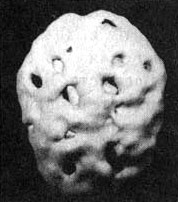

Мозг человека, употребляющего много кофеина и никотина

Трехмерное изображение поверхности, вид снизу. Обратите внимание на выраженное общее снижение активности, особенно в префронтальной коре и височных долях.

Как-то ко мне приехал знакомый — успешный бизнесмен. Он рассказал, что в последнее время ему трудно сосредоточиться, у него мало сил. Я знал, что в день он выпивает минимум по три кружки кофе и выкуривает по три пачки сигарет. Долгое время я думал, что у него синдром дефицита внимания (он плохо учился в школе, совершал импульсивные поступки и не мог долго сидеть на месте), и что он использовал никотин и кофеин в качестве стимулятора мозговой деятельности. Он был генеральным директором чрезвычайно успешной корпорации и не привык слушать чужие советы. Я рассказал ему про СДВ и сказал, что хватит заниматься псевдолечением при помощи лошадиных доз кофе и сигарет. Вместо этого лучше было бы заняться непосредственно лечением СДВ. Его первой реакцией был вопрос: нет ли у нас какого-нибудь природного средства для лечения СДВ, потому что ему не хочется принимать лекарства. Слегка изумленный, я ответил: «Так вы же принимаете целых два — никотин и кофеин, и они вполне могут вас уморить! Я же прописываю лекарство, которое действует гораздо эффективнее и при этом, если его принимают правильно, никого не убивает!»

Я предложил ему провести сканирование SPECT, чтобы с его помощью точнее определить состояние мозга. Кроме того, наглядные изображения могут стать лучшим аргументом против курения и кофе. Результаты сканирования стали неприятной неожиданностью даже для меня. Активность была заметно снижена по всей поверхности коры, и особенно в области префронтальной коры и височных долей. Я сказал своему знакомому, что ему надо найти другой стимулятор работы мозга, помимо кофе и никотина. В противном случае может получиться так, что он попросту окажется не в состоянии в полной мере вкусить радость успеха — у него не останется на это мозга. На протяжении нескольких недель он держался, но затем вновь вернулся к своим привычкам. И вот мне интересно: или сниженная активность височных долей «помогла» ему забыть то, что он увидел на изображениях SPECT, или очень низкая активность префронтальной коры не дает ему возможности в должной мере управлять собственными импульсами. И хотя я рекомендовал ему попробовать препарат, стимулирующий активность мозга (Ritalin или Adderall), он настоял на том, что хотел бы вылечить свой СДВ «естественным путем».